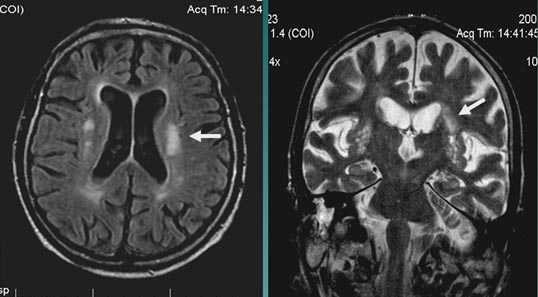

Лакунарное ишемическое ОНМК на фоне хронической сосудистой недостаточности.

Некоторые инфаркты при дисциркуляторной энцефалопатии протекают бессимптомно. Это «немые» инфаркты, которые, как правило, локализуются в глубоких отделах мозга и диагностируются только при МРТ. Этот случай показывает возможности выявление очага ограниченного ишемического ОНМК базальных ядер слева на фоне хронической ишемии.